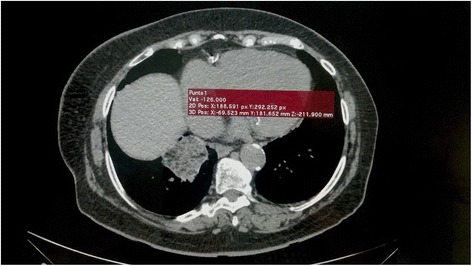

Vicks VapoRub®- chronic intranasal application led to pneumonia in this woman. An 85-year-old woman developed exogenous lipoid pneumonia (ELP), apparently due to long-term intranasal application of Vicks VapoRub® to relieve chronic rhinitis. She was found to have an elevated